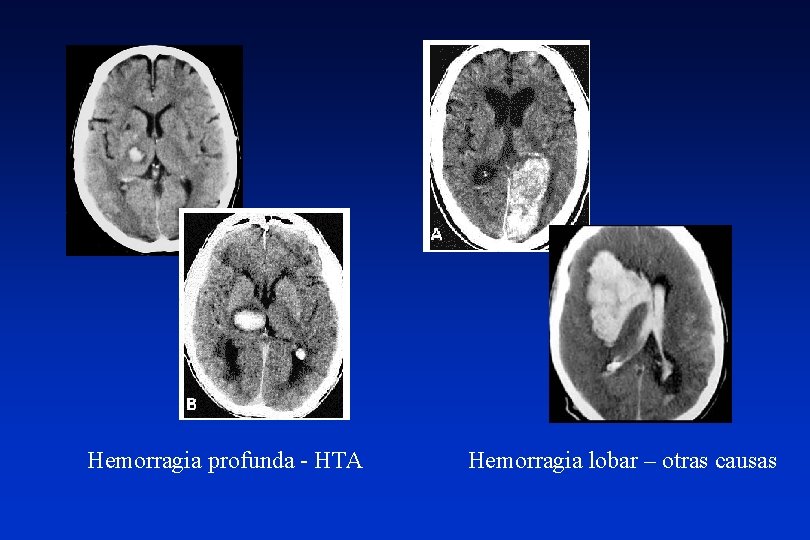

Hemorragia profunda - HTA Hemorragia lobar – otras causas

Causas y características hematomas intraparenquimatosos ETIOLOGIA Hipertensión arterial (40 -70%) LOCALIZACION* Ganglios de la base, cerebelo, tronco, sustancia blanca subcortical EDAD Mayores de 45 años Malformaciones vasculares (4 -10%) Lobares Jóvenes Angiopatía amiloidea (5 -10%) Lobares Ancianos Tumores cerebrales (2 -10%) Atípicas Anticoagulación, fibrinolisis (9 -14%) Lobares Drogas simpaticomiméticas Indeterminada (10%) Ancianos Jóvenes